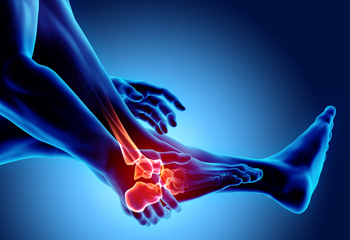

Causes of Outer Foot Pain

Outer foot pain can result from various conditions that affect the bones, ligaments, and joints. Ankle sprains occur when the ligaments are stretched or torn, leading to pain and instability on the outer side of the foot. Arthritis can cause inflammation in the joints, resulting in stiffness and discomfort that worsens with movement. A bunionette, or tailor’s bunion, forms at the base of the fifth toe, creating pressure and pain along the outer edge of the foot. Cuboid syndrome develops when the cuboid bone shifts out of alignment, often causing sharp pain and difficulty walking. Additionally, fifth metatarsal fractures involve a break in the long bone on the outer foot, leading to swelling and tenderness. If you have pain in this part of your foot, it is suggested that you consult a podiatrist who can determine what the cause is, and offer appropriate treatment solutions.

Foot Pain

Foot pain can be extremely painful and debilitating. If you have a foot pain, consult with one of our podiatrists from Comprehensive Footcare Clinic - Hawaii. Our doctors will assess your condition and provide you with quality foot and ankle treatment.

Foot pain is a very broad condition that could be caused by one or more ailments. The most common include:

Diagnosis

To figure out the cause of foot pain, podiatrists utilize several different methods. This can range from simple visual inspections and sensation tests to X-rays and MRI scans. Prior medical history, family medical history, and any recent physical traumatic events will all be taken into consideration for a proper diagnosis.

Treatment

Treatment depends upon the cause of the foot pain. Whether it is resting, staying off the foot, or having surgery; podiatrists have a number of treatment options available for foot pain.

Foot Pain

The feet, being the foundation of the body, carry all of the body’s weight and are therefore prone to experiencing pain and discomfort. If you are experiencing foot pain, it is important to determine where in the foot you are experiencing this pain to help discover the cause of it. While pain can be experienced virtually anywhere in the foot, the most common sites of foot pain are in the heel and ankle.

Heel pain can be due to a multitude of conditions including plantar fasciitis, Achilles tendinitis, and heel spurs. Pain experienced in the ankle can be a sign of an ankle sprain, arthritis, gout, ankle instability, ankle fracture, or nerve compression. In more serious cases, pain in the foot can be a sign of improper alignment or an infection.

Foot pain can be accompanied by symptoms including redness, swelling, stiffness and warmth in the affected area. Whether the pain can be described as sharp or dull depends on the foot condition behind it. It is important to visit your local podiatrist if your foot pain and its accompanying symptoms persist and do not improve over time.

Depending on the location and condition of your foot pain, your podiatrist may prescribe certain treatments. These treatments can include but are not limited to prescription or over-the-counter drugs and medications, certain therapies, cortisone injections, or surgery.

If you are experiencing persistent foot pain, it is important to consult with your foot and ankle doctor to determine the cause and location. He or she will then prescribe the best treatment for you. While milder cases of foot pain may respond well to rest and at-home treatments, more serious cases may take some time to fully recover.